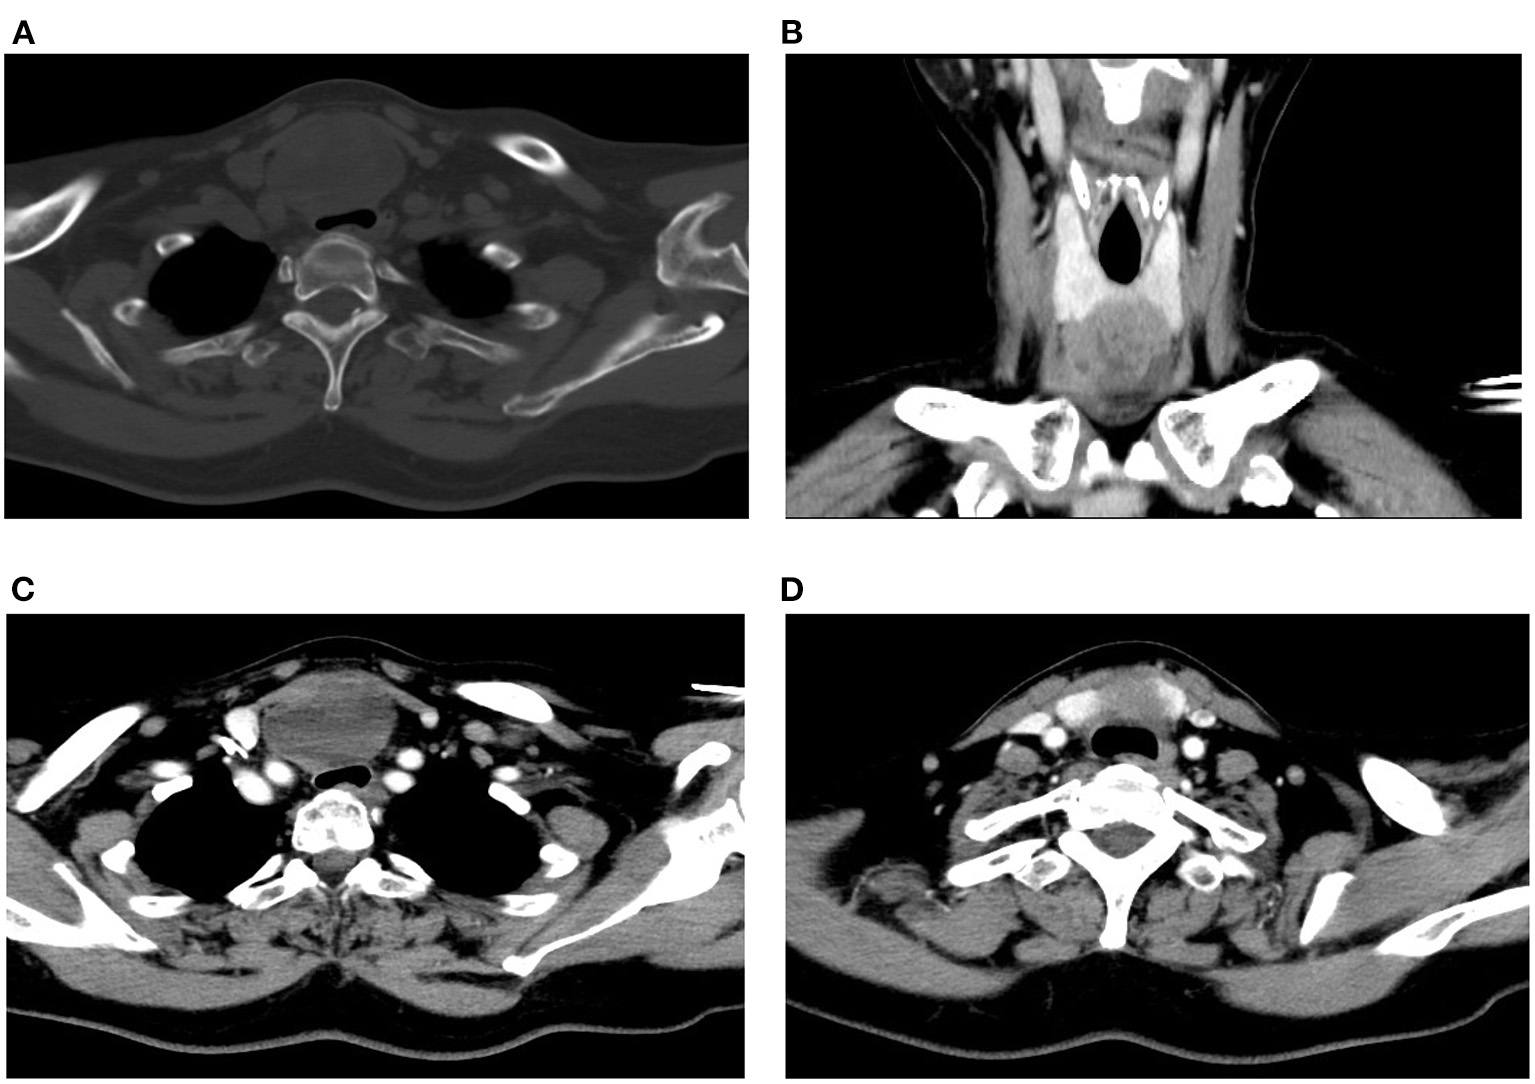

Figure 3

Preoperative CT scan of the patient. (A) Plain CT of the neck (horizontal plane). (B) CT scan of the neck (coronal plane). (C, D) Contrast-enhanced CT of the neck (horizontal plane).

A Blood test showed no obvious abnormalities. The level of thyroid hormone and calcitonin is in the normal range. No abnormalities were found in the laryngoscopy, chest X-ray, and chest CT. Contrast-enhanced ultrasonography showed a heterogeneous echoic, cystic-solid mixed mass ~48.8 × 37.2 mm in the isthmus of the thyroid gland. The mass is with clear boundary, regular shape. In total, 0.6 ml perflubutane microspheres were injected through the elbow intravenous for CEUS. The isthmus nodule was mostly equally enhanced and partially no enhancement. The peripheral nodule showed annular enhancement. No obvious enlarged lymph nodes were observed in the cervical region. The mass was classified as TI-RADS 3 (Figure 2). CT scan showed a mass lesion in or below the isthmus of the thyroid gland. The mass was heterogeneous density. There are microcalcifications and liquefaction necrosis areas inside the mass. The average CT value is 28 HU. The edge of the mass is mostly clear. The contrast-enhanced CT demonstrated heterogeneous enhancement. The degree of enhancement is lower than that of the normal thyroid gland. The average CT value is 58 HU. There are multiple small lymph nodes in the I-II area of the cervical region. The CT could not establish a confirmed diagnosis but a low-grade tumor could not be ruled out (Figure 3).